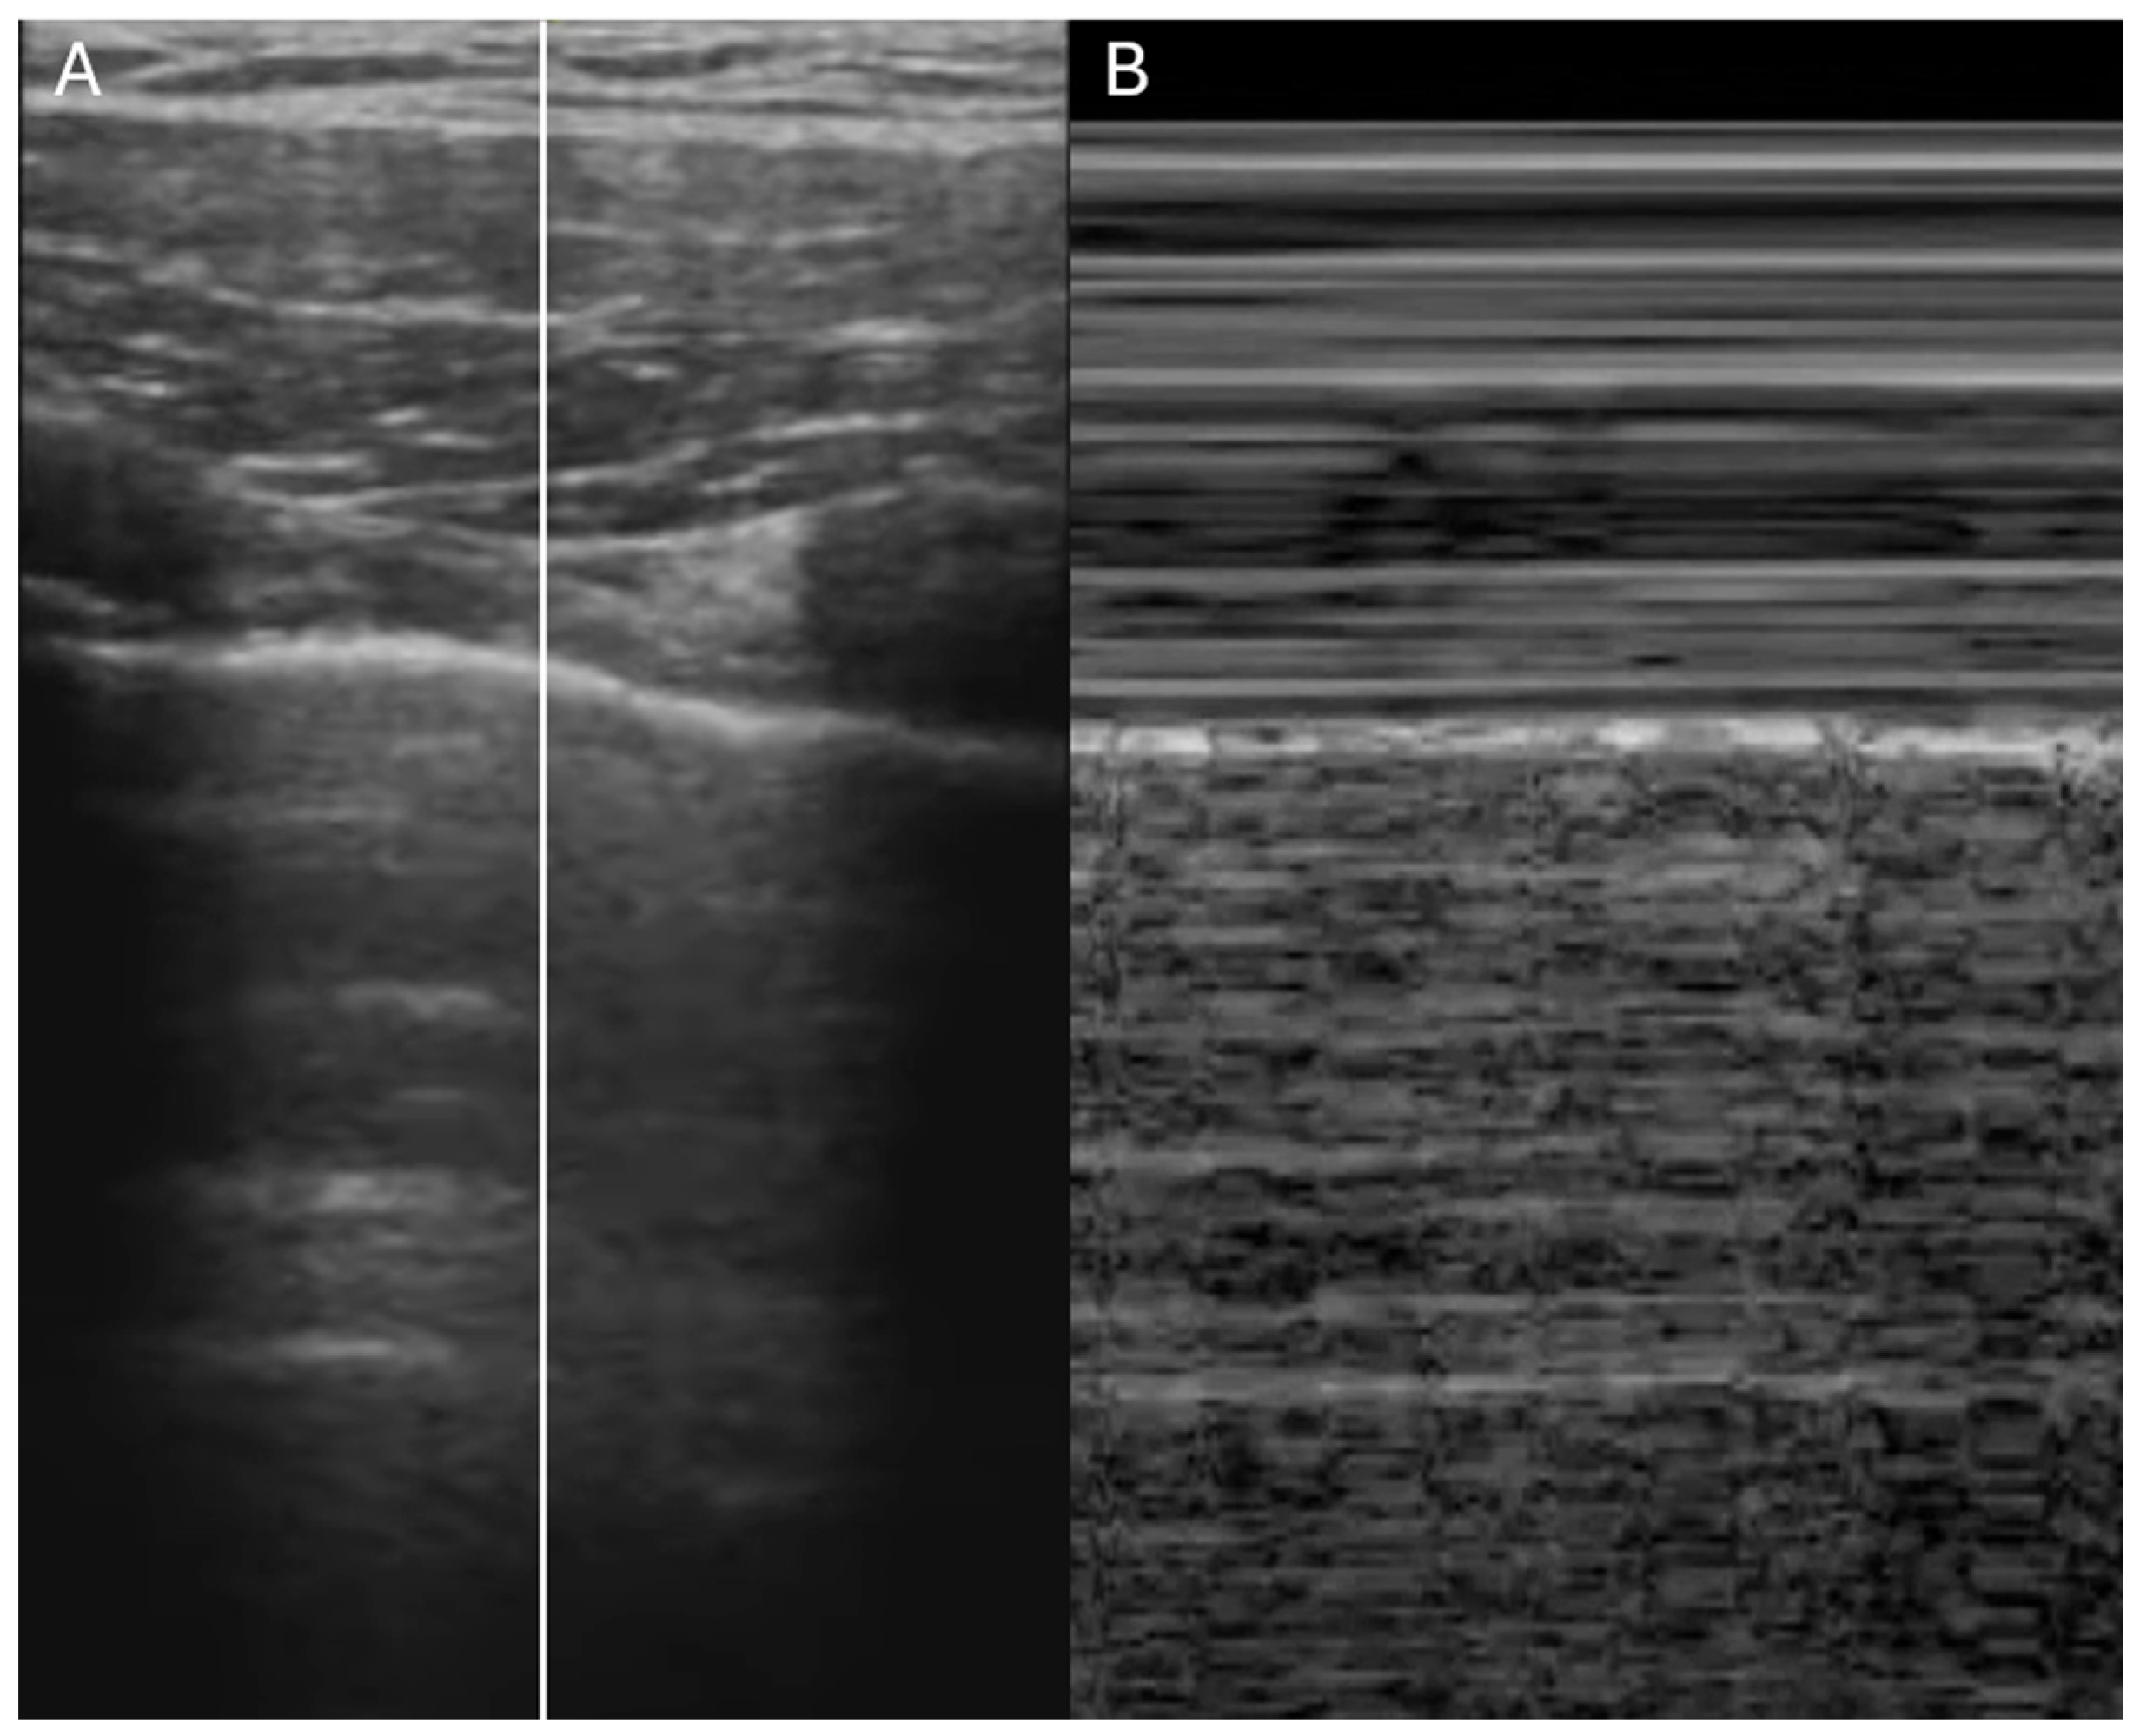

- Is the IVC dilated or collapsible?

- Assessment of right atrial pressure

- Ruge, M.; Marhefka, G.D. IVC measurement for the noninvasive evaluation of central venous pressure. J. Echocardiogr. 2022, 20, 133–143. [Google Scholar] [CrossRef]

- Rudski, L.G.; Lai, W.W.; Afilalo, J.; Hua, L.; Handschumacher, M.D.; Chandrasekaran, K.; Solomon, S.D.; Louie, E.K.; Schiller, N.B. Guidelines for the echocardiographic assessment of the right heart in adults: A report from the American Society of Echocardiography endorsed by the European Association of Echocardiography, a registered branch of the European Society of Cardiology, and the Canadian Society of Echocardiography. J. Am. Soc. Echocardiogr. 2010, 23, 685–713. [Google Scholar]